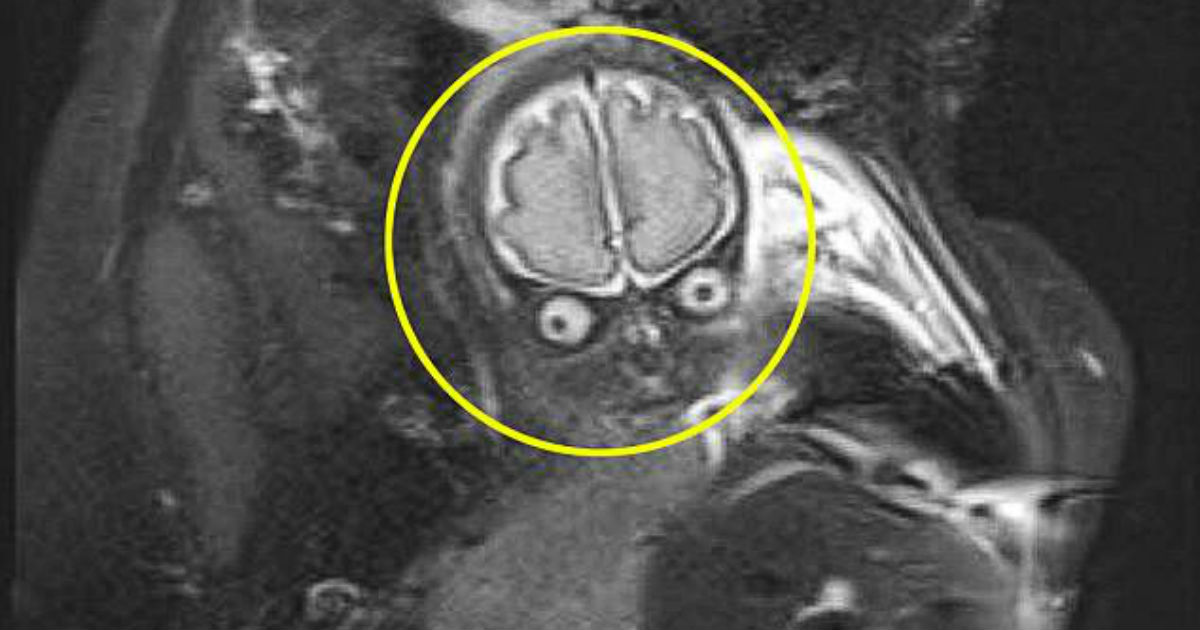

Laura Thomas e Matthew Tansley levaram um susto ao ver a ressonância magnética de seu bebê Lucas com 30 semanas de gestação.

Eles teriam visto a aparência do filho no exame e se surpreenderam com a imagem.

Foi preciso fazer uma ressonância após o médico ter visto fluido em excesso no cérebro do bebê durante um de seus ultrassons. Mas, foi constatado que não tinha nenhuma complicação.

Mesmo assim, a criança passou por vários exames. O casal então decidiu compartilhar a foto da ressonância em suas redes sociais e a imagem viralizou.